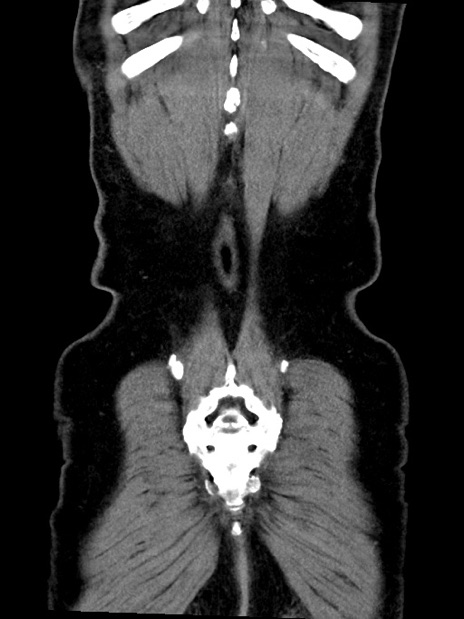

横断像